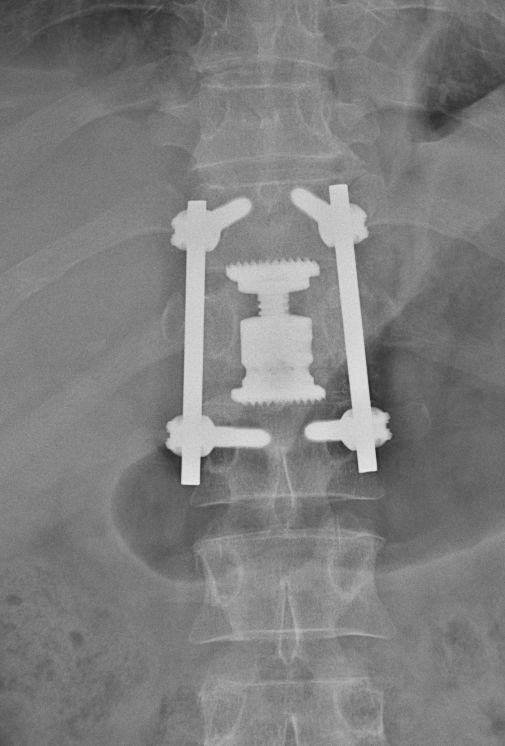

• Tříštivá zlomenina obratle T12 po kombinovaném ošetření vnitřním fixátorem v rozsahu T11-L1

Jednotlivé procedury se při operačním výkonu prolínají a fungují společně. Pro zajištění primární pooperační stability ze zadního přístupu používáme v krční i torakolumbální oblasti vnitřní fixátory. Jejich součástí jsou šrouby případně háky a spojovací tyče překlenující poraněný páteřní segment. Z předního přístupu jsou nejčastěji aplikovány kostní štěpy nebo klece přemostěné dlahou v krční oblasti, expandibilní klece a fixátory v torakolumbální oblasti. Všechny fixační prvky jsou vyrobeny ze slitiny titanu, která omezuje negativní stíny na vyšetření CT a jsou MR kompatibilní. Pro dosažení trvalé kostní stability používáme přemostění poraněného obratle nebo obratlů kostními štěpy z lopaty kosti kyčelní nebo syntetickou náhradu (trikalciumfosfát, hydroxiapatit).